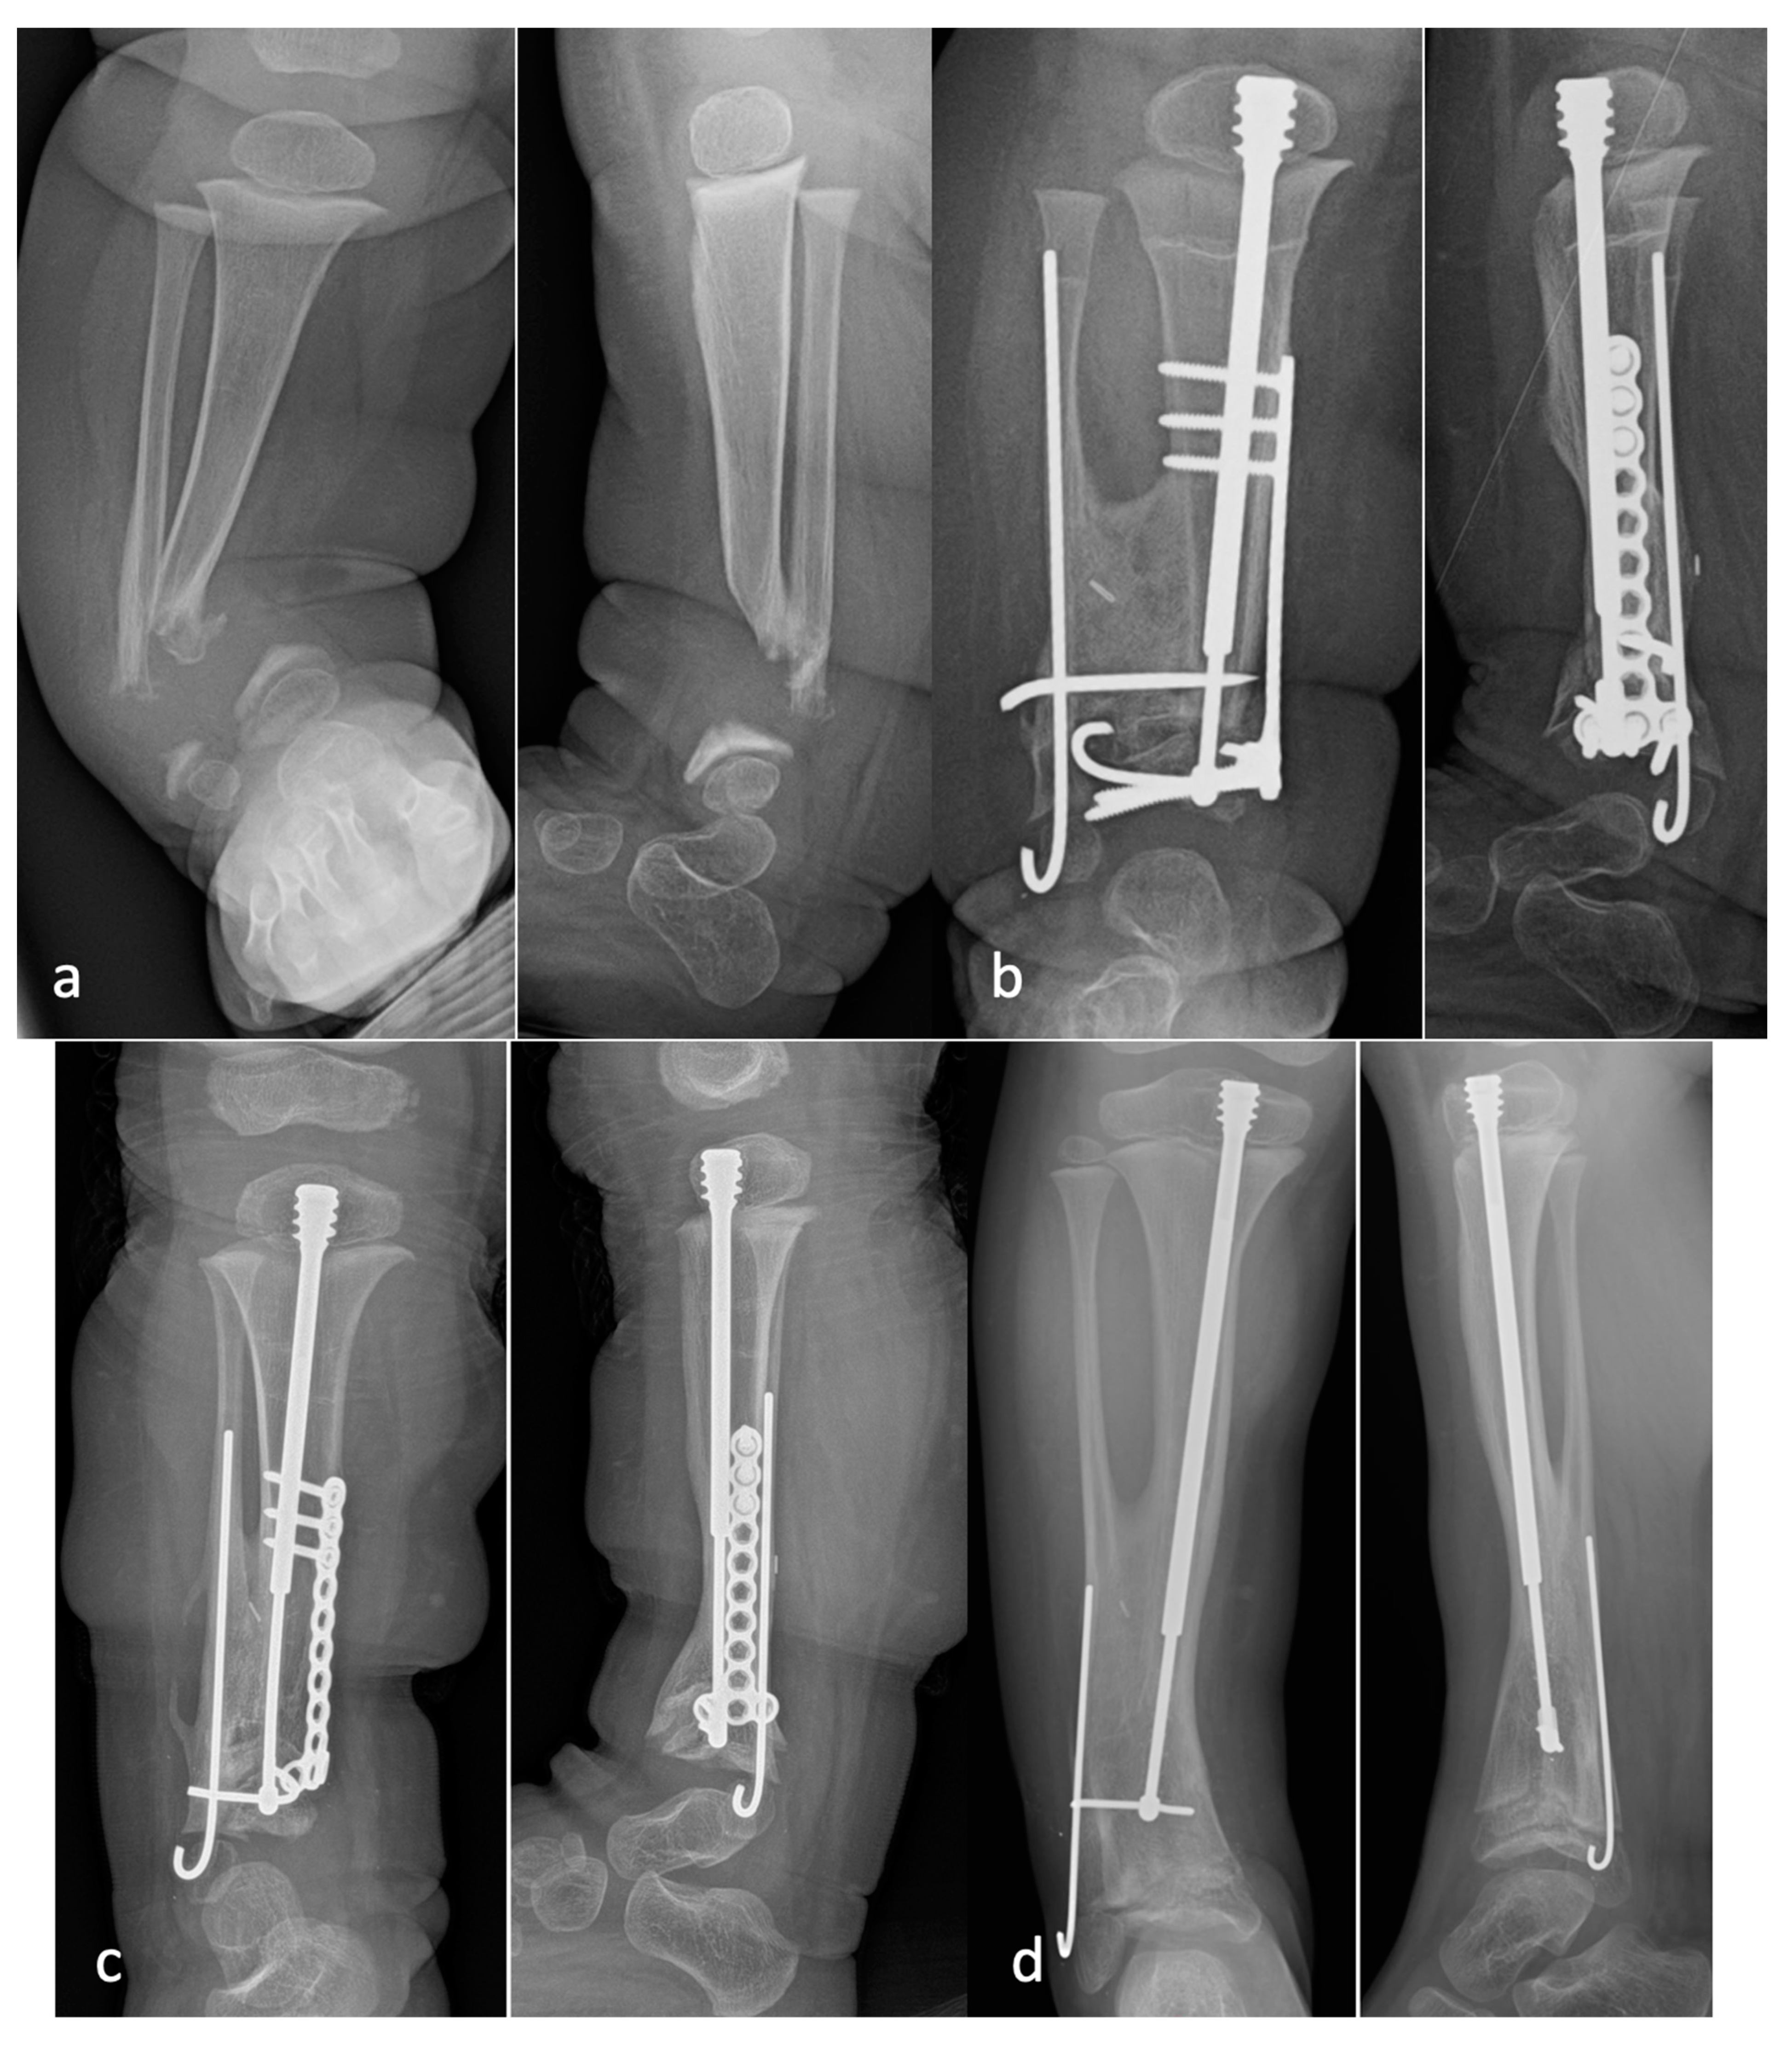

Figure 7. Radiographs of a patient who underwent a cross-union with internal fixation: (a) preoperative AP and lateral radiographs demonstrating a large bone defect and small distal metaphyseal segments of the tibia and fibula (Type 4C); (b) AP and lateral radiographs taken 12 weeks after surgery show a well-healed cross-union with bridging between the tibia and fibula, as well as filling of the bony defects; (c) AP and lateral radiographs taken 1 year after surgery with growth of the bone at both ends and telescoping of the FD rod to the level of the cross-union; (d) AP and lateral radiographs taken at 2.5 years after surgery, after a one-rod exchange, with a solid cross-union and no refracture.